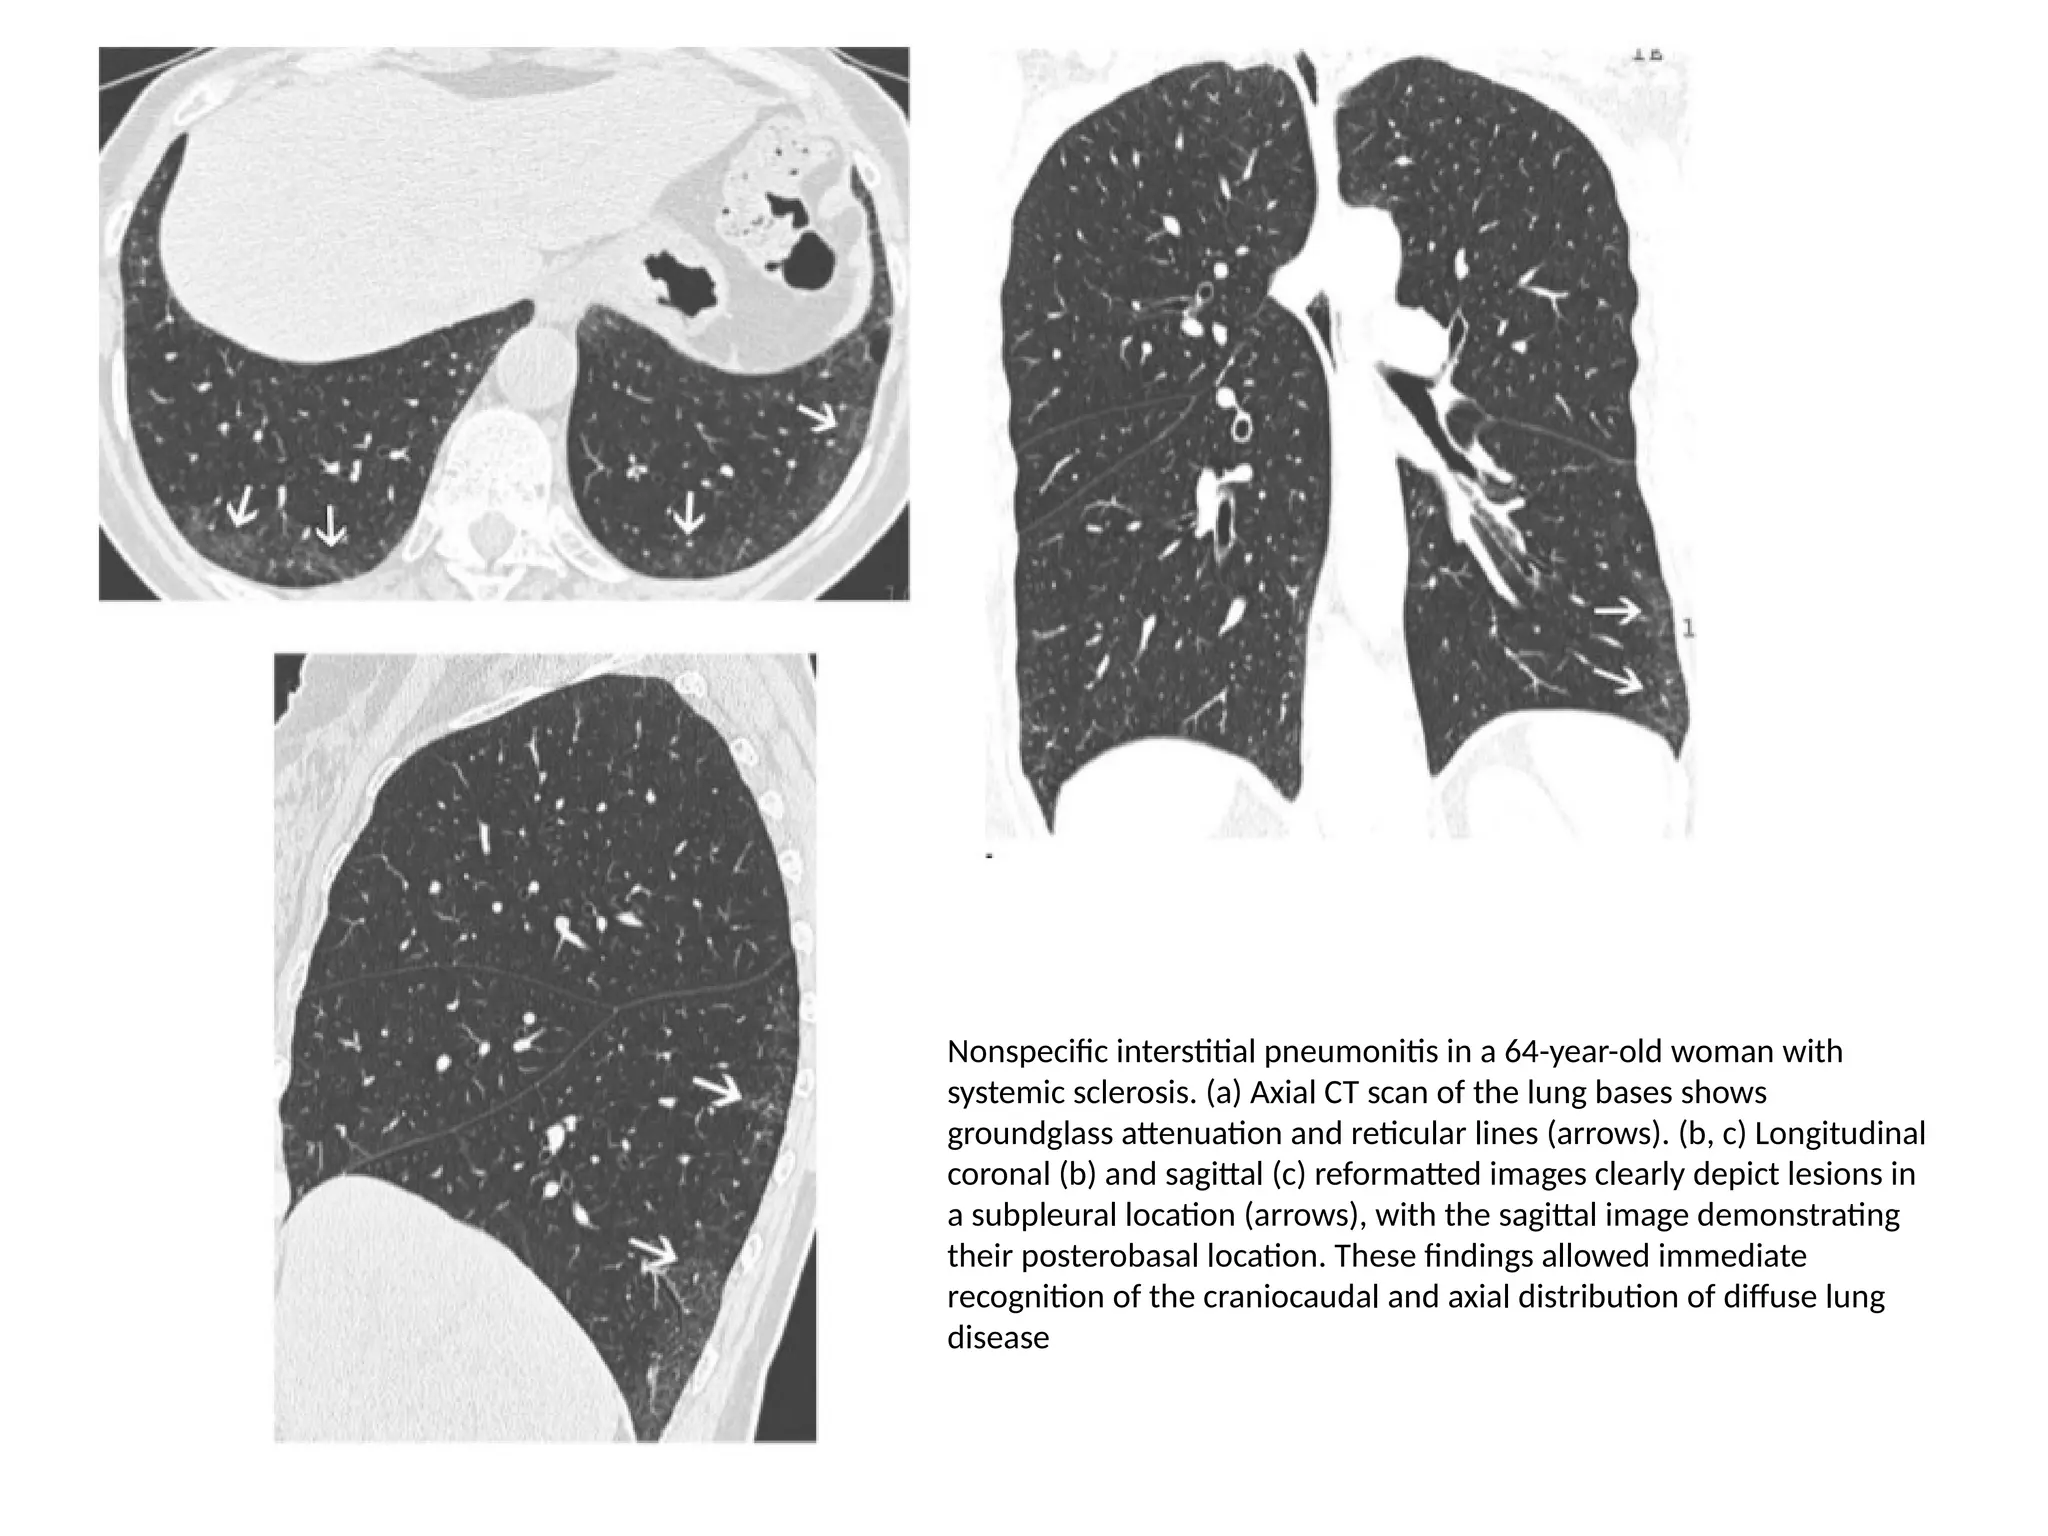

Nonspecific interstitial pneumonitis in a 64-year-old woman with

systemic sclerosis. (a) Axial CT scan of the lung bases shows

groundglass attenuation and reticular lines (arrows). (b, c) Longitudinal

coronal (b) and sagittal (c) reformatted images clearly depict lesions in

a subpleural location (arrows), with the sagittal image demonstrating

their posterobasal location. These findings allowed immediate

recognition of the craniocaudal and axial distribution of diffuse lung

disease

Nonspecific interstitial pneumonitisin a 64-year-old woman with systemic sclerosis. (a) Axial CT scan of the lung bases shows groundglass attenuation and reticular lines (arrows). (b, c) Longitudinal coronal (b) and sagittal (c) reformatted images clearly depict lesions in a subpleural location (arrows), with the sagittal image demonstrating their posterobasal location. These findings allowed immediate recognition of the craniocaudal and axial distribution of diffuse lung disease